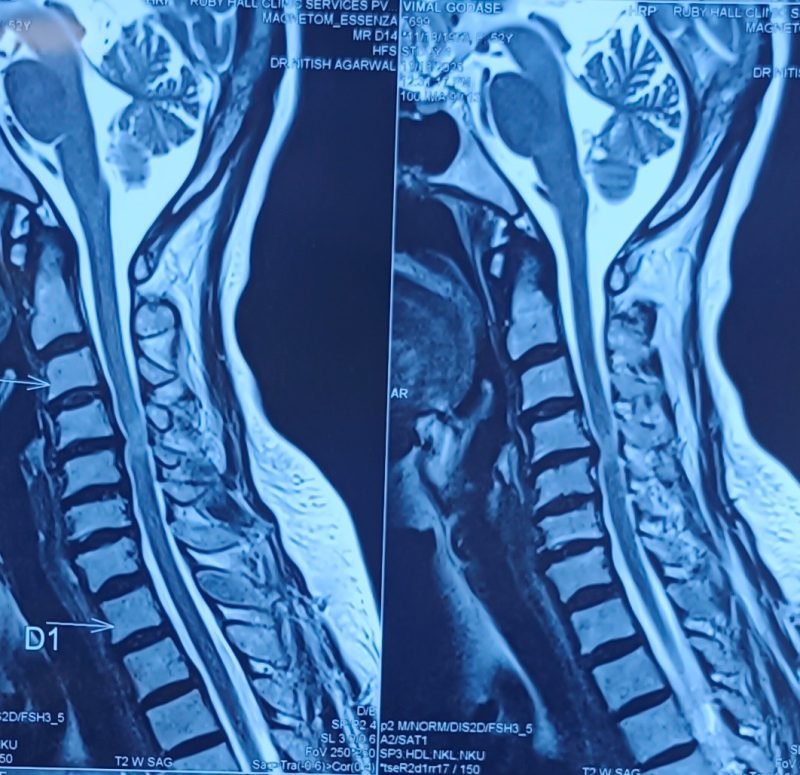

Condition:

Cervical disc prolapse in which the herniated disc compresses the nerve roots and spinal cord, often associated with spinal cord edema.

Symptoms:

Neck pain, numbness in hands, weakness, difficulty in walking, and coordination problems.

Treatment:

Anterior Cervical Discectomy and Fusion (ACDF) – The damaged disc is removed and the spine is stabilized using a bone graft or implant to relieve pressure on the spinal cord and nerves.